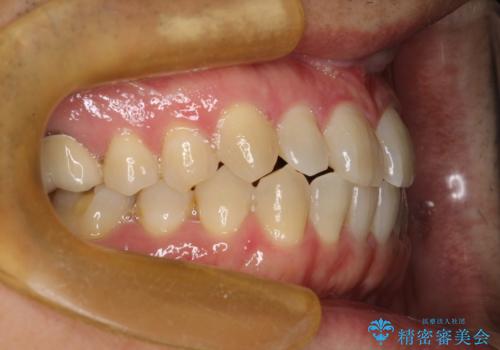

前歯の隙間 インビザラインにて整った歯並びへ

- 前歯の隙間が気になるとのことで来院されました。

インビザラインにて矯正治療を行うこととしました。

下の歯と歯の間にわずかに隙間をつくり、上の前歯の隙間を閉じました。